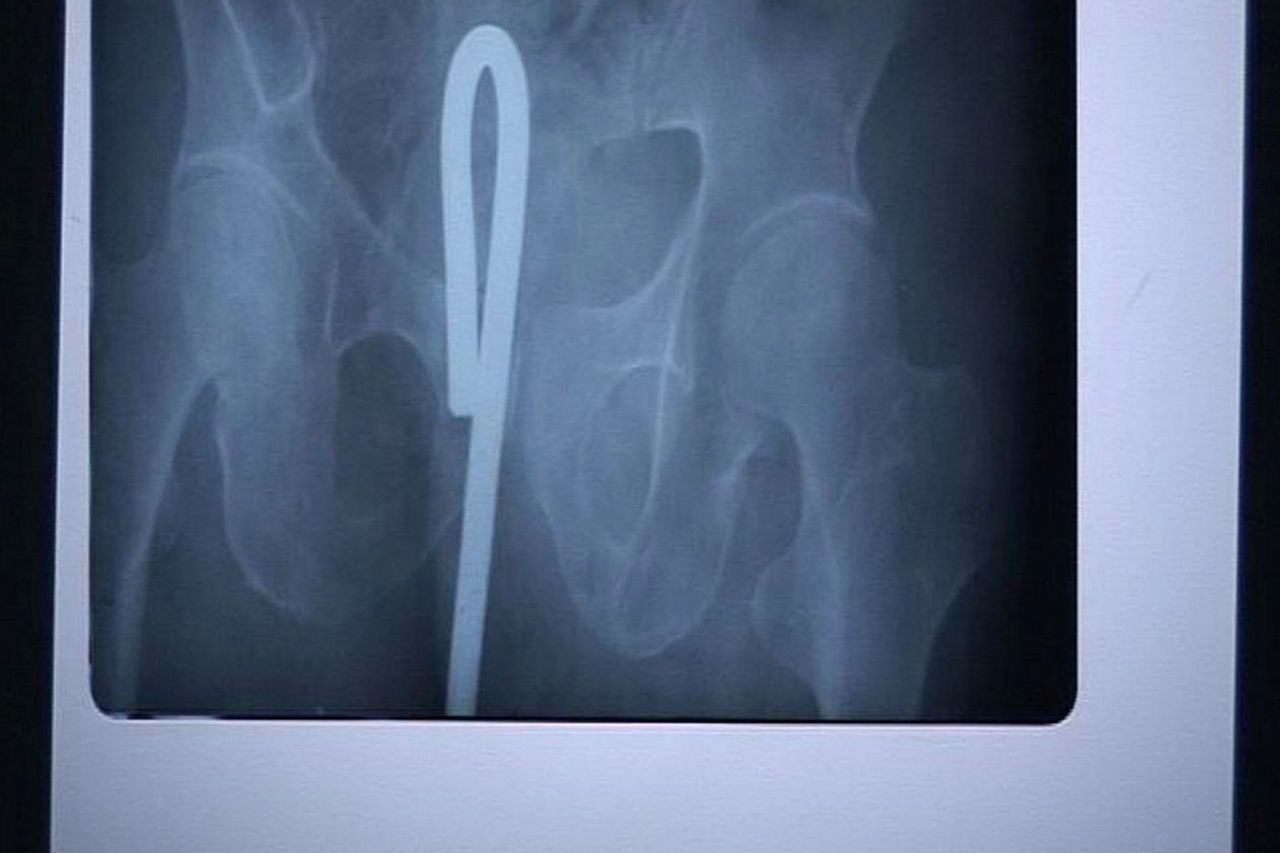

同じマンガで、アソコが痛いと主婦がやって来て、レントゲン撮ったら編み物に使うかぎ針が。なんで?と混乱する主婦…が、そう言えば学生の頃にオ〇二ーしててかぎ針使ってて抜けなくなり、そのうち出てくるとほっといて忘れてたって…。